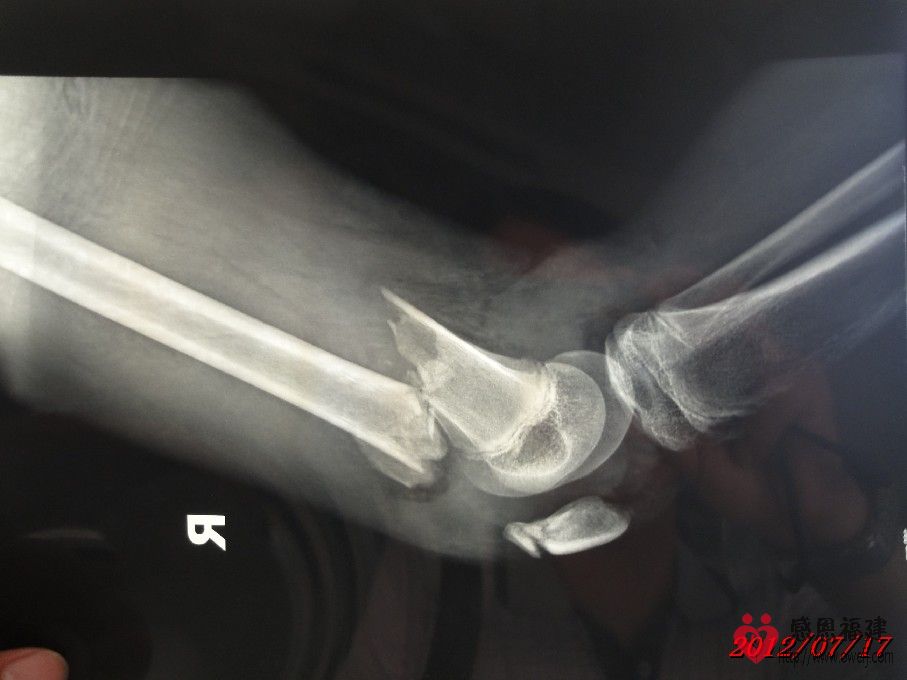

1、事故情况:2012年7月1日14:30左右,智在同学骑邻居的无牌照XGJ125摩托车载着两个同学在北洋小学附近的123县道与停在路旁的无牌照货车发生碰撞(据孩子介绍货车基本占了半边马路,当时对面刚好有车驶来,智在为了避免和对面车发生碰撞往右避让,结果撞上了停在路旁的货车的左后角),导致摩托车撞坏、智在右大腿骨折和另外一位同学大腿骨折。

2、住院情况:事故发生后家人将智在送往闽清县医院治疗,医院同意住院并可安排第二天手术;但智在是一家四口中唯一没有残疾的(由于残疾的父亲在医院照顾智在,哑巴的母亲精神不好还时常跑回老家又不会照顾人,导致眼睛残疾的小弟弟几天没吃上两顿饭),家人和亲戚为了智在治疗后不留下后遗症,最后决定送往福州市第二医院治疗,并于当晚存了2,000元住院费并办好住院手续。但由于家境贫寒,智在的父亲和亲戚到处借债(有的500,有的1,000……),好不容易东拼西凑才筹集到手术费用(现在已经累计存入医院38,000元),手术于7月11日进行,效果还比较理想,但出院时间待定。

1、2012年7月25日上午,智在父亲和姑妈帮智在办妥了出院手续,整个住院在医院花费了36,878.39元,其他的交通费、生活费、误工费等均未包括在内;